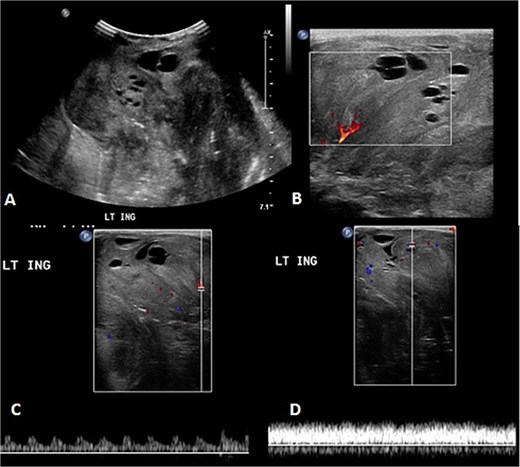

A 2-month-old girl was being followed for a suspected hemangioma on her left hand since birth. She was initially started on oral propranolol therapy but only received one dose, due to family concerns about possible side effects. The patient presented at the emergency room because of ulceration. It was observed clinically that the lesion had grown from 1.5 × 1.5 cm to 4 × 2 cm (Fig. 5). A biopsy of the lesion was taken. Ultrasound showed a partially defined large heterogeneously hyperechoic mass with internal vascularity on color Doppler with arterial and venous waveform giving atypical features of hemangioma (Fig. 6). Biopsy was done using FoundationOne Heme. The result showed stable microsatellite status and when we tested the tumor mutational burden, it showed two mutations per megabase. On MRI, a large lobulated subcutaneous soft tissue mass measuring 3.7 × 6.1 × 4.6 cm in dimensions was seen originating from the medial aspect of the left hand (Fig. 7). Internal flow voids, intermediate signal intensity on T1-weighted images, hyperintense signal on short tau inversion recovery (STIR)-weighted images, and noticeable heterogeneous enhancement on postcontrast sequences were all observed in the lesion. These imaging results raised suspicions of a malignant lesion.

Initial imaging utilizing gray scale and color Doppler US. (A) A gray scale US image showing a large heterogeneous lesion predominantly hyperechogenic in echotexture with a partially defined margin and (B–D) color Doppler US and spectral waveform showing internal vascularity within the lesion with the presence of arterial and venous waveform. The aforementioned findings are atypical for hemangiomas.